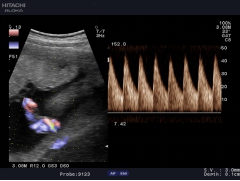

血流剖面圖

常規(guī)用多普勒方式測量血流速度只能測量某一點的速度,因此,測量血流量具有一定的局限性,日立阿洛卡推出的血流速度分布圖技術(shù)成功解決了此問題, 通過此技術(shù),醫(yī)生可以方便地得到整個血管剖面上的每一點的血流速度,從而準確計算出血管的流量。血流速度分布圖技術(shù)也可用于心排量的計算。

DDD二維、彩色雙幅動態(tài)實時顯示技術(shù)

二維、彩色雙福動態(tài)實時顯示技術(shù)允許系統(tǒng)同步顯示二維圖像和彩色多普勒圖像,便于同時觀察組織結(jié)構(gòu)和血流動力學(xué)變化。使原來只能在兩個顯示器上實現(xiàn)的功能在同一顯示器上就能實現(xiàn),使感興趣區(qū)不會在頻繁的轉(zhuǎn)換模式時丟失,而且為臨床介入治療準確穿刺定位提供了實時監(jiān)測手段,避免周圍血管損傷。